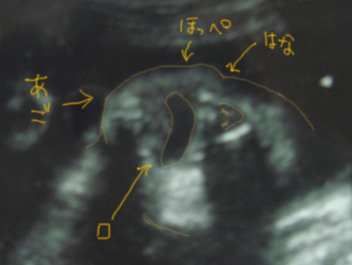

総合病院の2Dのエコーでも顔がはっきり(?)見えるようになりました(・∀・)ktkr

ちょうどエコーで見てたときにレナさんが

でっかいあくびをグァーーっとして

目をこすっていた所が見れた(^ω^)

超激カワ!!っと一人でテンション↑↑状態でした

もちろん心の中で

(*画像はちょうど先生がその瞬間を撮影してくれた時のもの(^ω^)センセーありが㌧GJです)